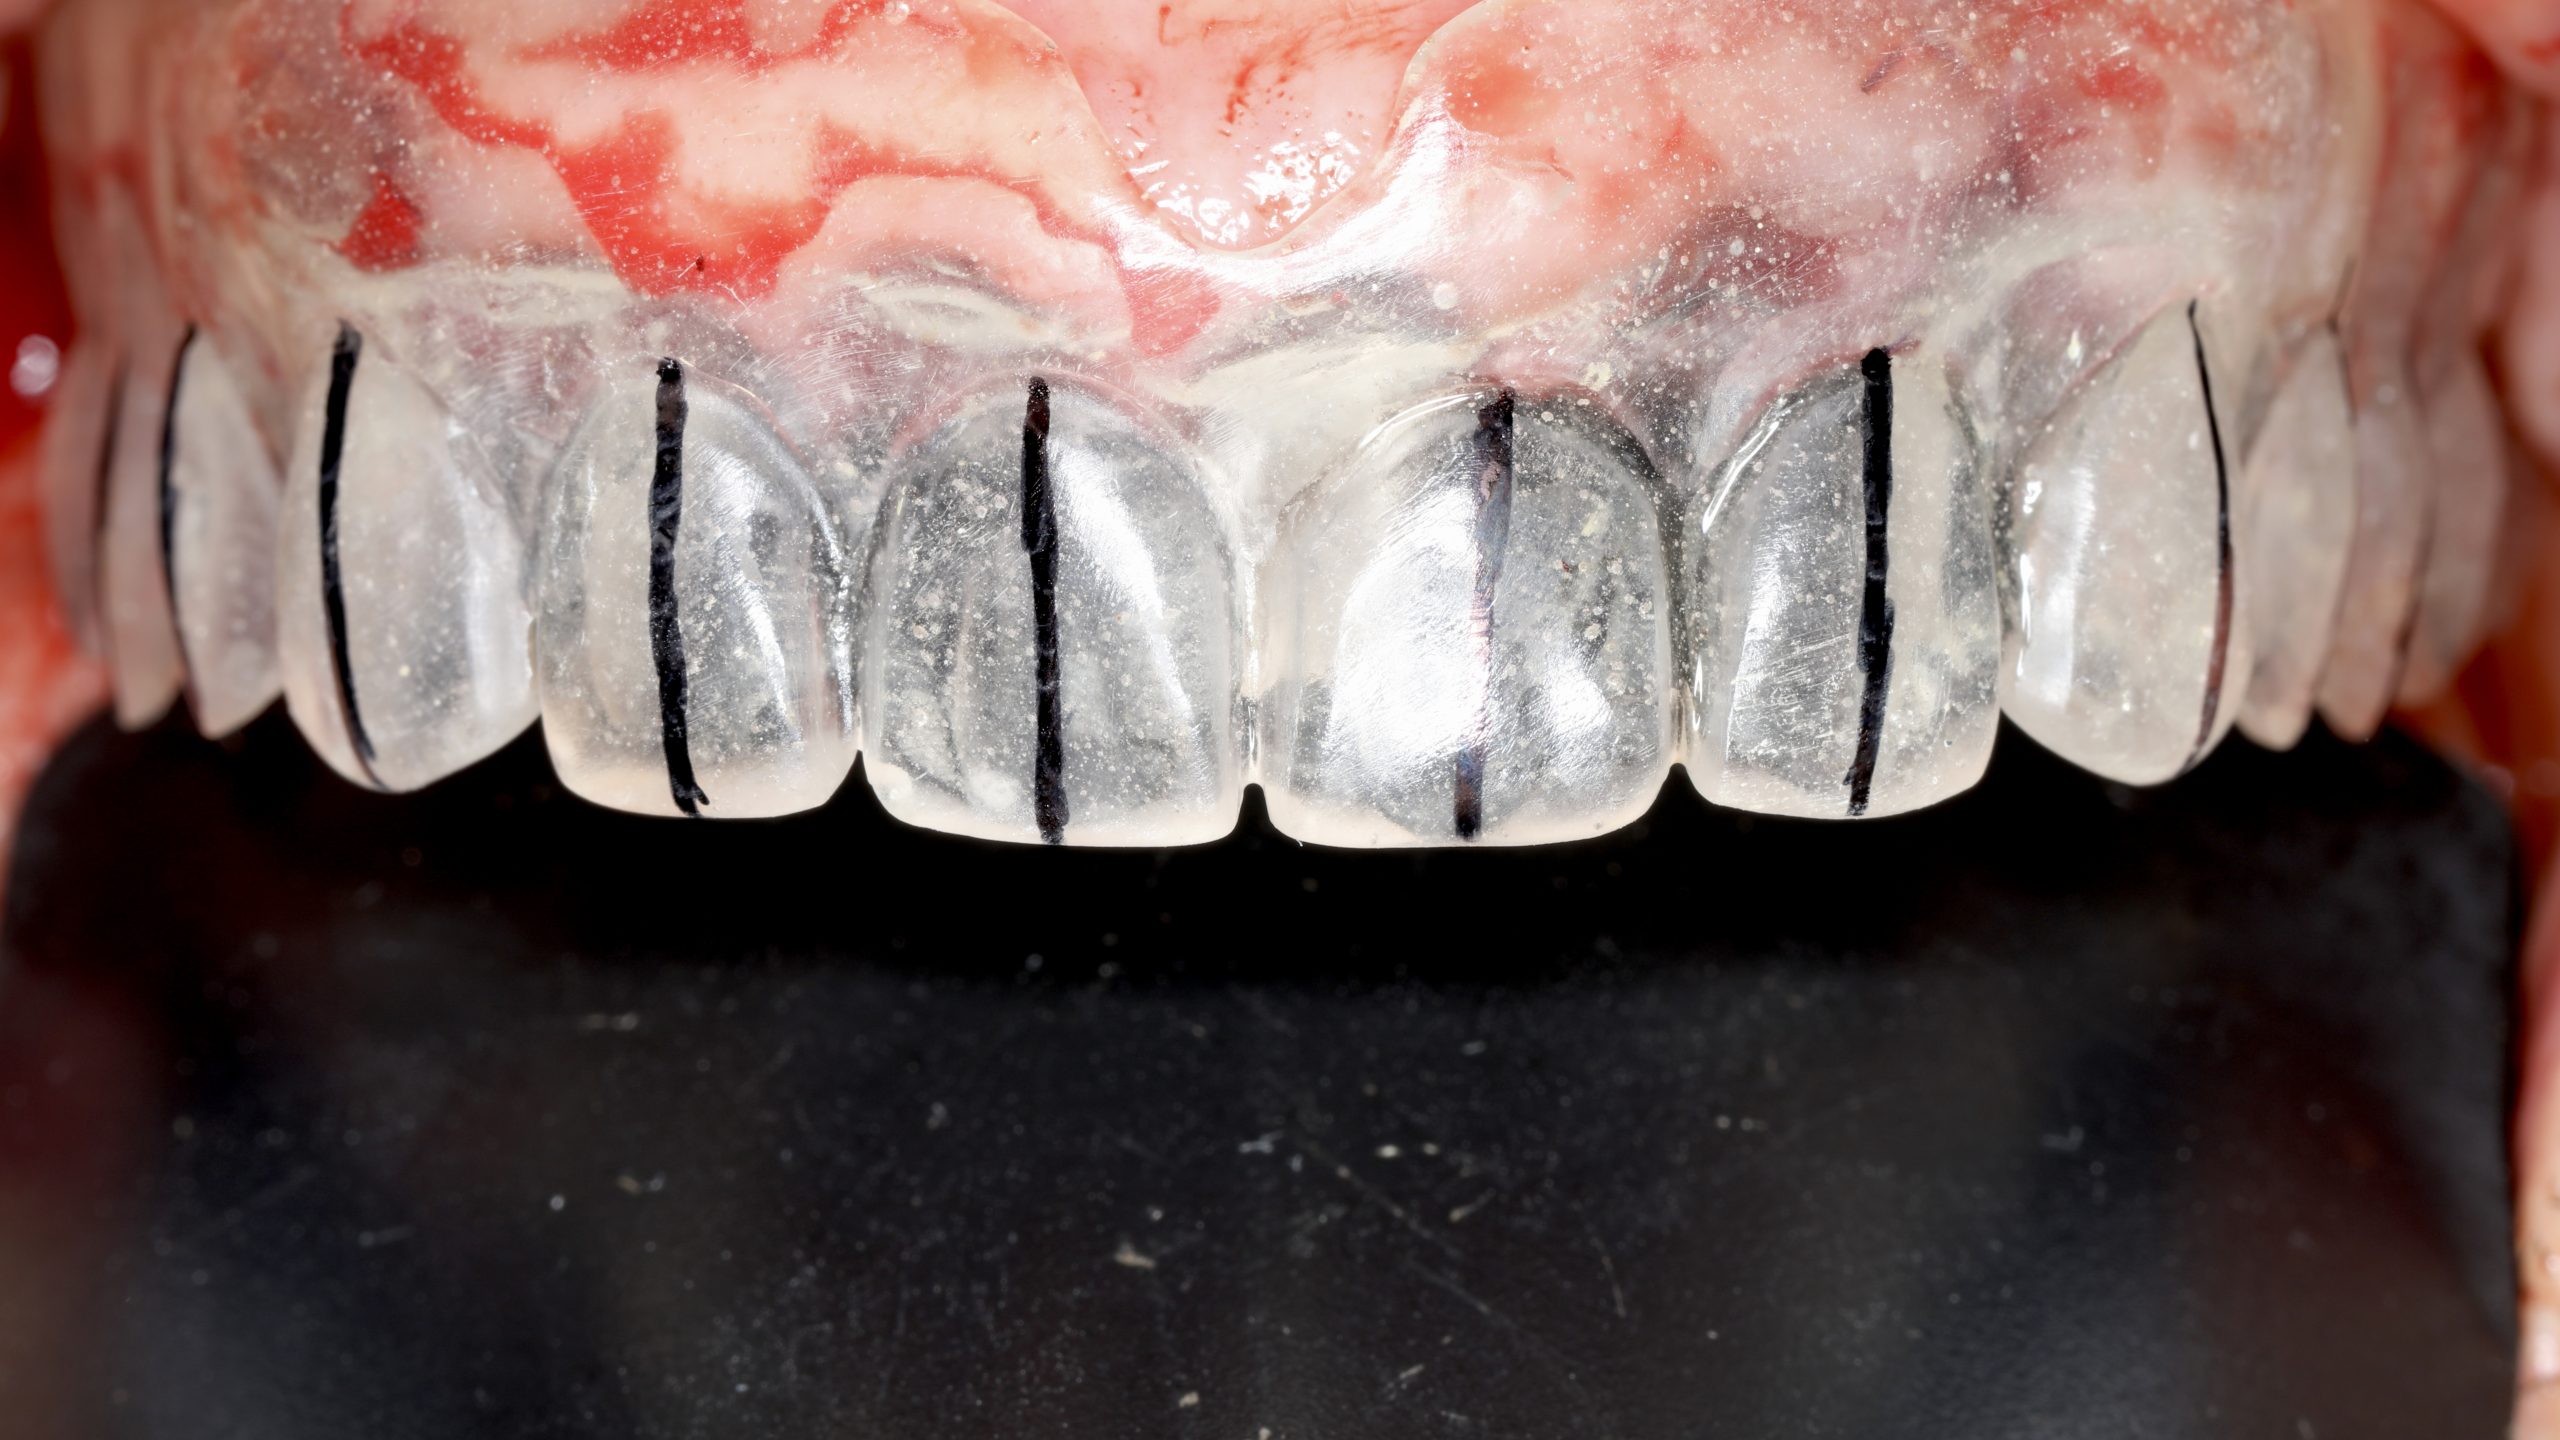

Complete upper rehabilitation directly screwed in zirconia – ceramic

Case study carried out with Athena Smile Pelekanos (GR ) : dott . Stavros Pelekanos